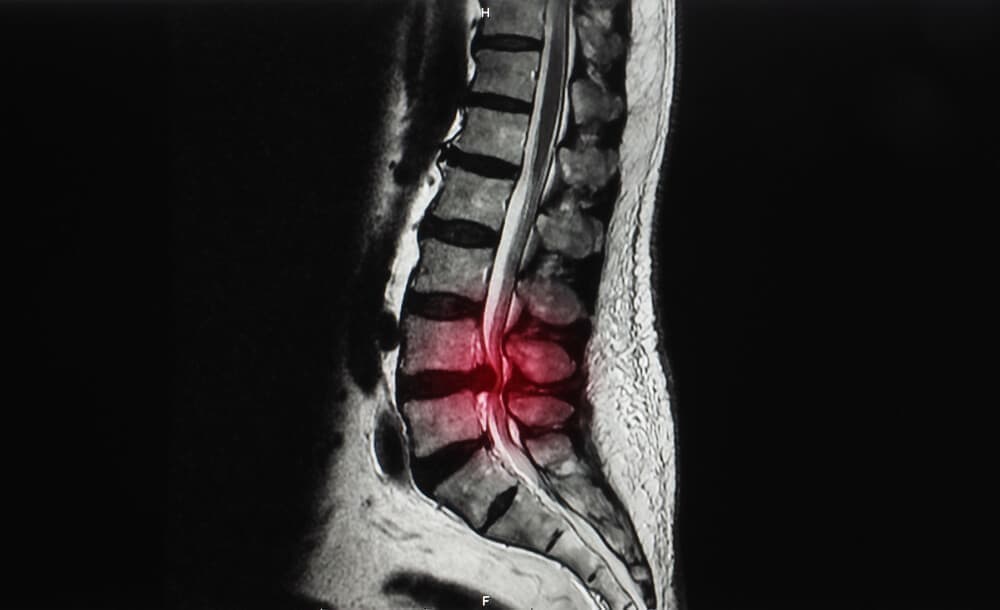

腰椎すべり症とは?

背骨(脊柱)にある椎骨という骨にズレが生じている状態のことを腰椎すべり症と呼ばれています。

背骨(脊柱)は、椎骨がいくつも連結して形成されています。

腰椎すべり症は大きく3つに分類されます。

腰椎変性・腰椎分離・形成不全性の3つの種類です。

腰椎変性すべり症は中高年以降の女性に多い傾向にあり、変性してしまうことで発症します。

腰椎分離すべり症は発育期に進行することが多く、通常は繋がっているべき骨の繋がりが絶たれてしまった状態が進行することで引き起こります。

形成不全性すべり症は、先天性で発育の問題で引き起こされます。

これは非常に稀な症状で、比較的若年層に多い傾向です。